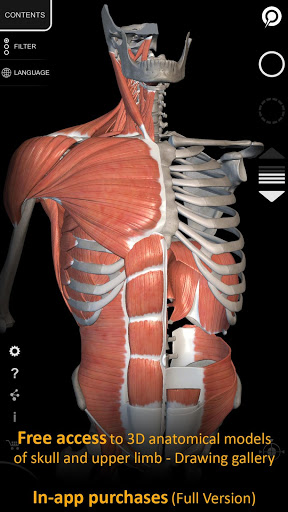

"Anatomía - Atlas 3D" permite estudiar la anatomía humana de forma fácil e interactiva.

A través de una interfaz sencilla e intuitiva es posible observar cada estructura anatómica desde cualquier ángulo.

Los modelos anatómicos 3D son especialmente detallados y con texturas de hasta una resolución de 4k.

MODELOS ANATÓMICOS 3D

• Sistema musculoesquelético